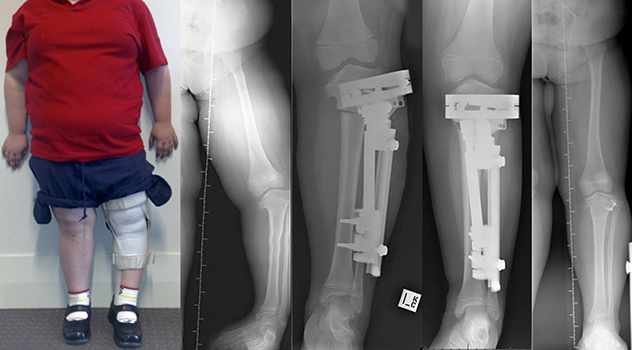

Deformation Correction

Deformity correction is a procedure to straighten a bone that is bent or twisted in a way that is not normal. After the bone is straightened, the arm, leg, or foot has normal alignment and function. Deformities can be corrected in two different ways:

- All at once during a surgical procedure (called acute correction)

- Slowly over the course of several weeks or months (called gradual correction)